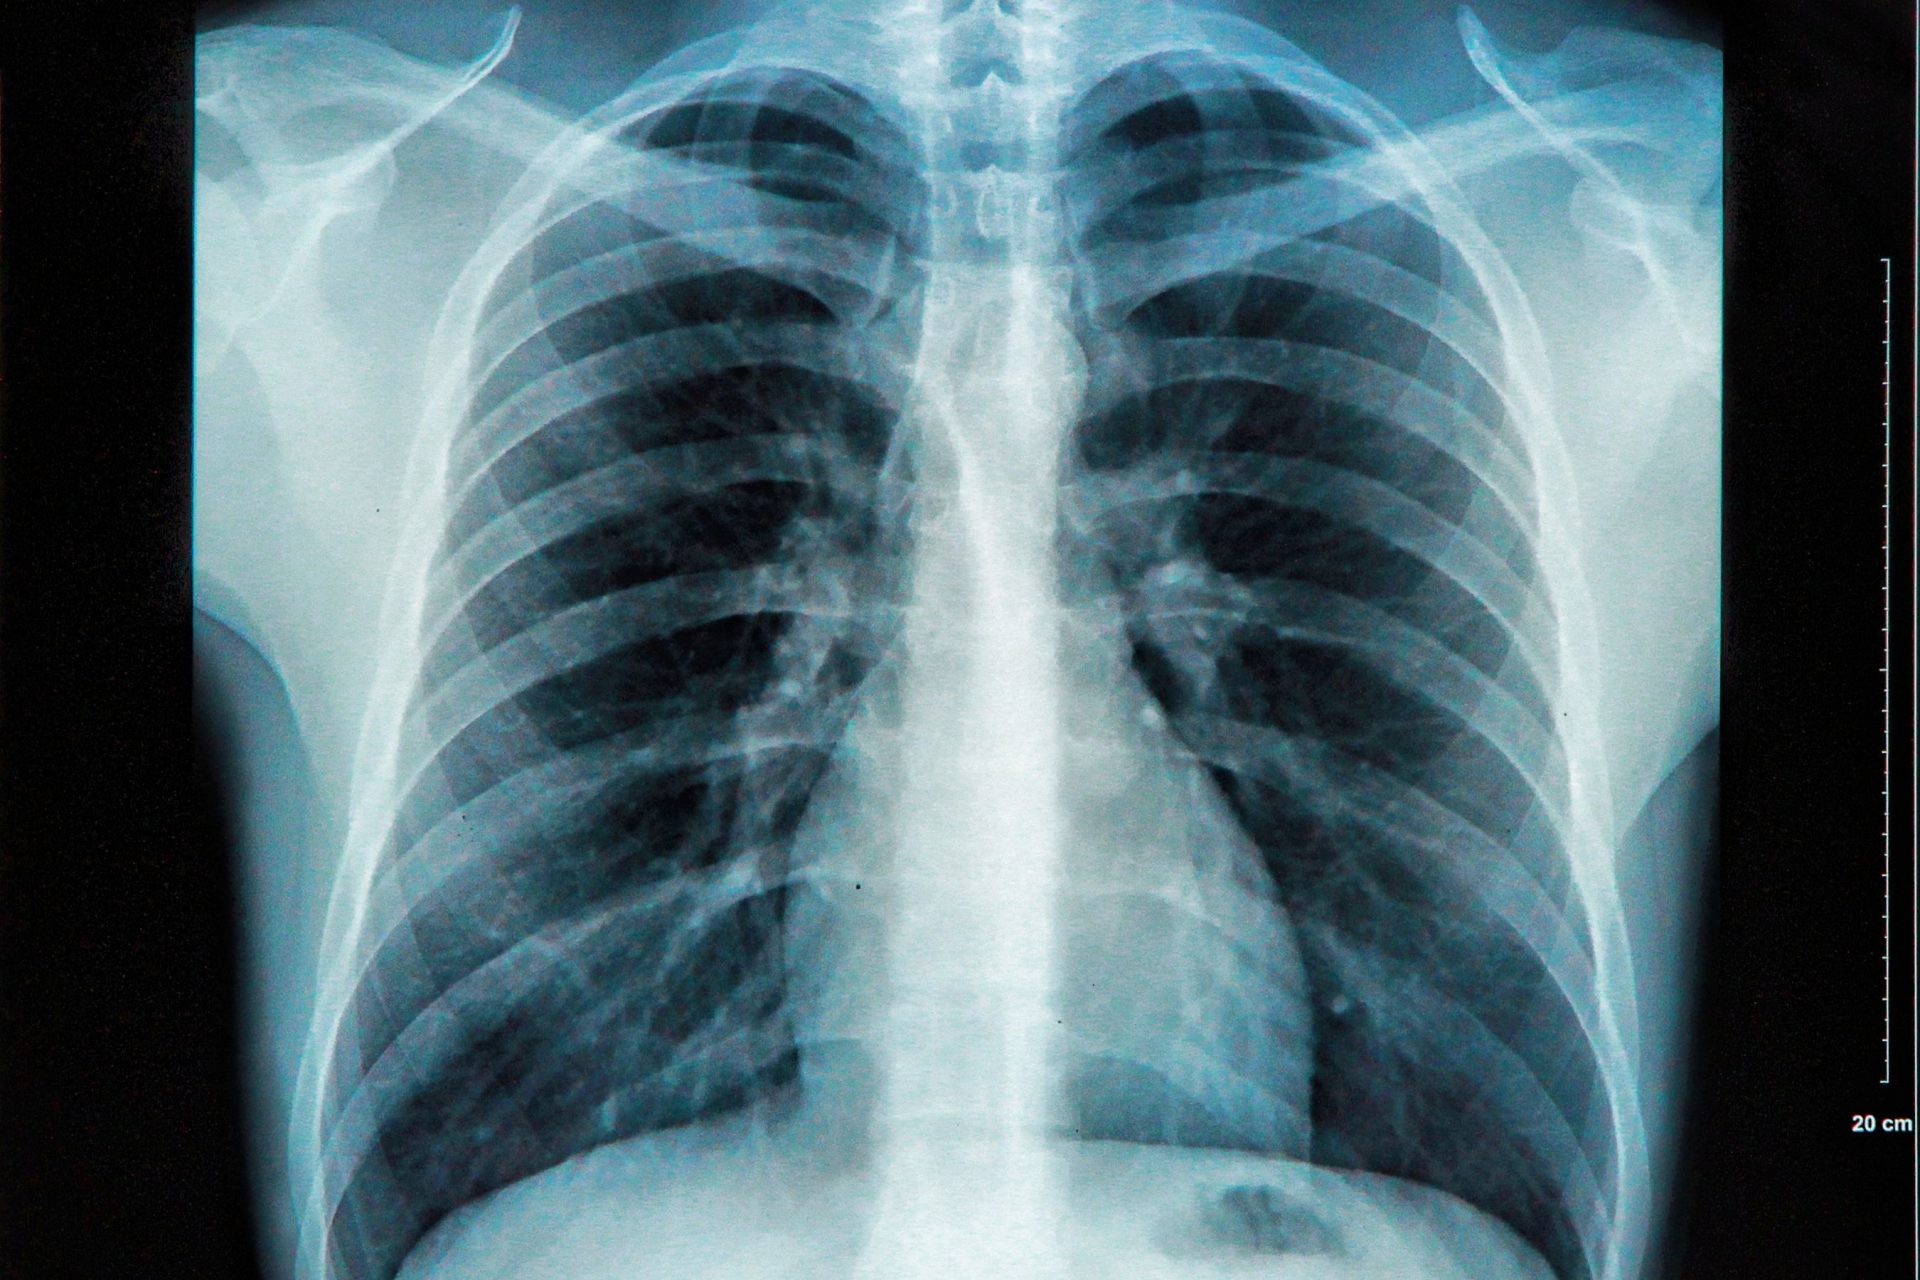

An X-ray of the chest reveals basic information about the size and shape of the person’s heart, blood vessels, and lungs.